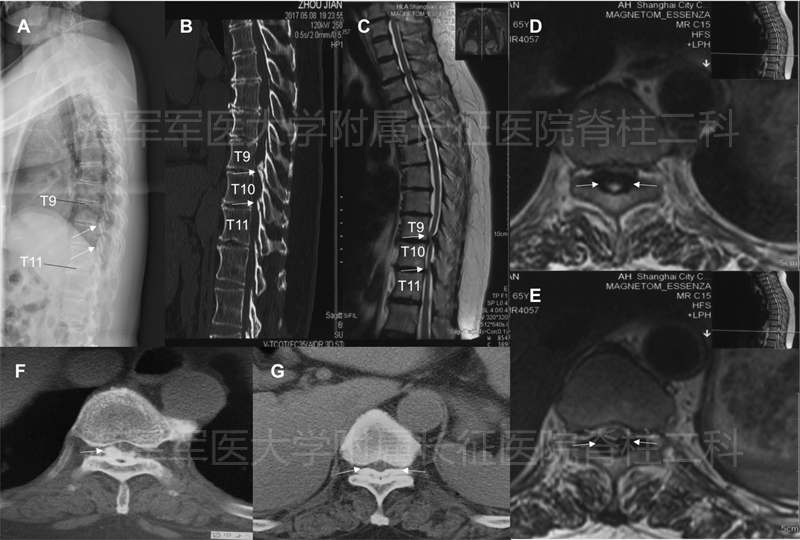

4.胸椎后纵韧带骨化症椎体骨化物复合体可控前移术

术前MRI和CT

术后平片

术后CT